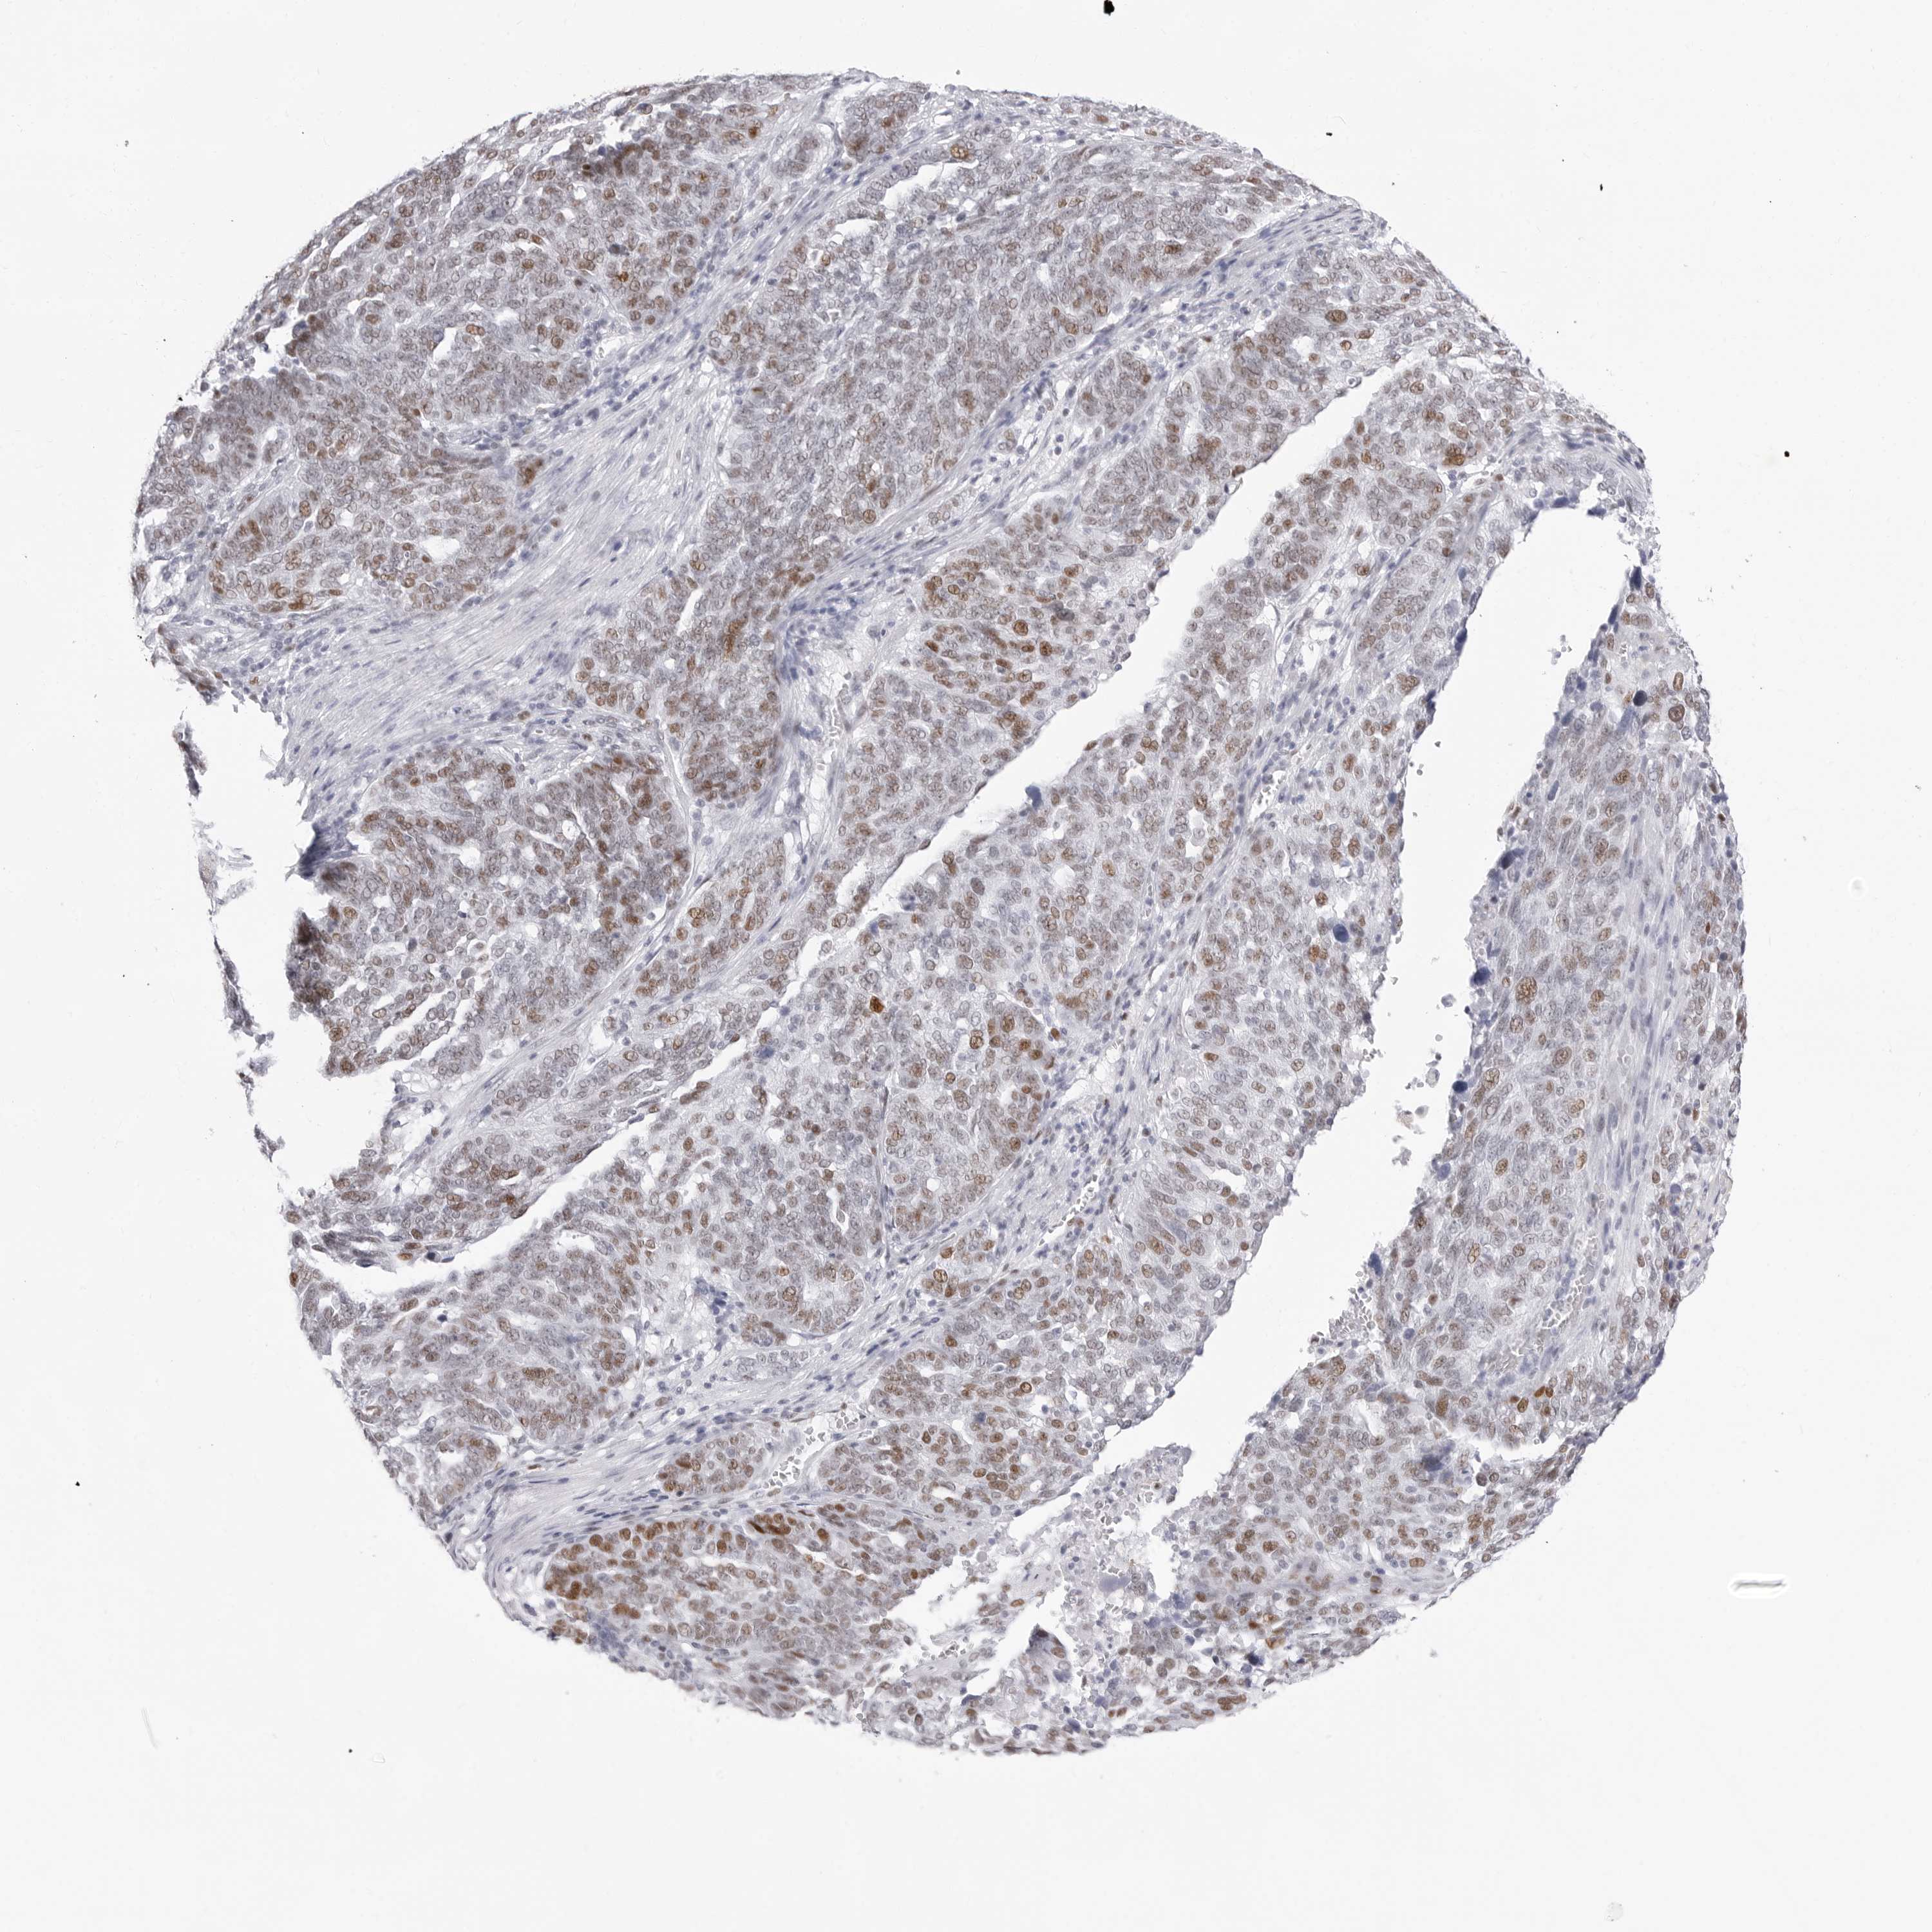

OVARIAN CANCER - Protein expressioni

A mouse-over function shows sample information and annotation data. Click on an image to view it in a full screen mode. Samples can be filtered based on level of antibody staining by selecting one or several of the following categories: high, medium, low and not detected. The assay and annotation is described here.

Note that samples used for immunohistochemistry by the Human Protein Atlas do not correspond to samples in the TCGA dataset.

Antibody stainingi

Antibody staining in the annotated cell types in the current human tissue is reported as not detected, low, medium, or high, based on conventional immunohistochemistry profiling in selected tissues. This score is based on the combination of the staining intensity and fraction of stained cells.

Each image is clickable and will lead to virtual microscopy that enables deeper exploration of all samples and also displays staining intensity scores, fraction scores and subcellular localization as well as patient and tissue information for each sample.

Antibody HPA028136

Antibody HPA030518

Antibody HPA030520

Cystadenocarcinoma, serous, NOS

Carcinoma, endometroid

Cystadenocarcinoma, mucinous, NOS

Carcinoma, NOS